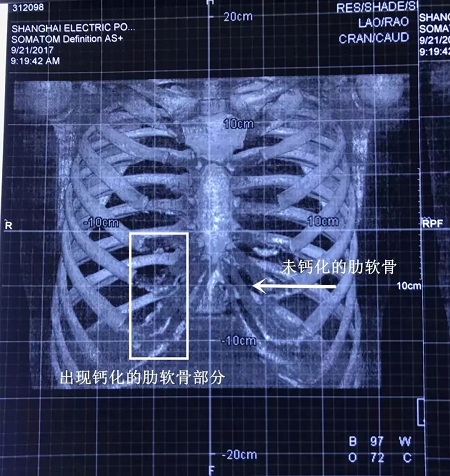

▼鈣化肋軟骨和未鈣化肋軟骨的影像區(qū)別

如上圖所示,鈣化了的肋軟骨和硬骨一樣,都是呈同樣密度的白色顯示,而正常的肋軟骨密度顯示是透明狀。

輕微鈣化的肋軟骨不會(huì)影響隆鼻效果,不過(guò)對(duì)醫(yī)師的雕刻技術(shù)是一個(gè)考驗(yàn)。

▼輕微鈣化的肋軟骨